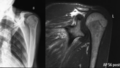

- Posterosuperior rotator-cuff edema in traumatic tear.jpg Alexandre.laedermann

06:53, 15 June 2020

720 × 305; 126 KB